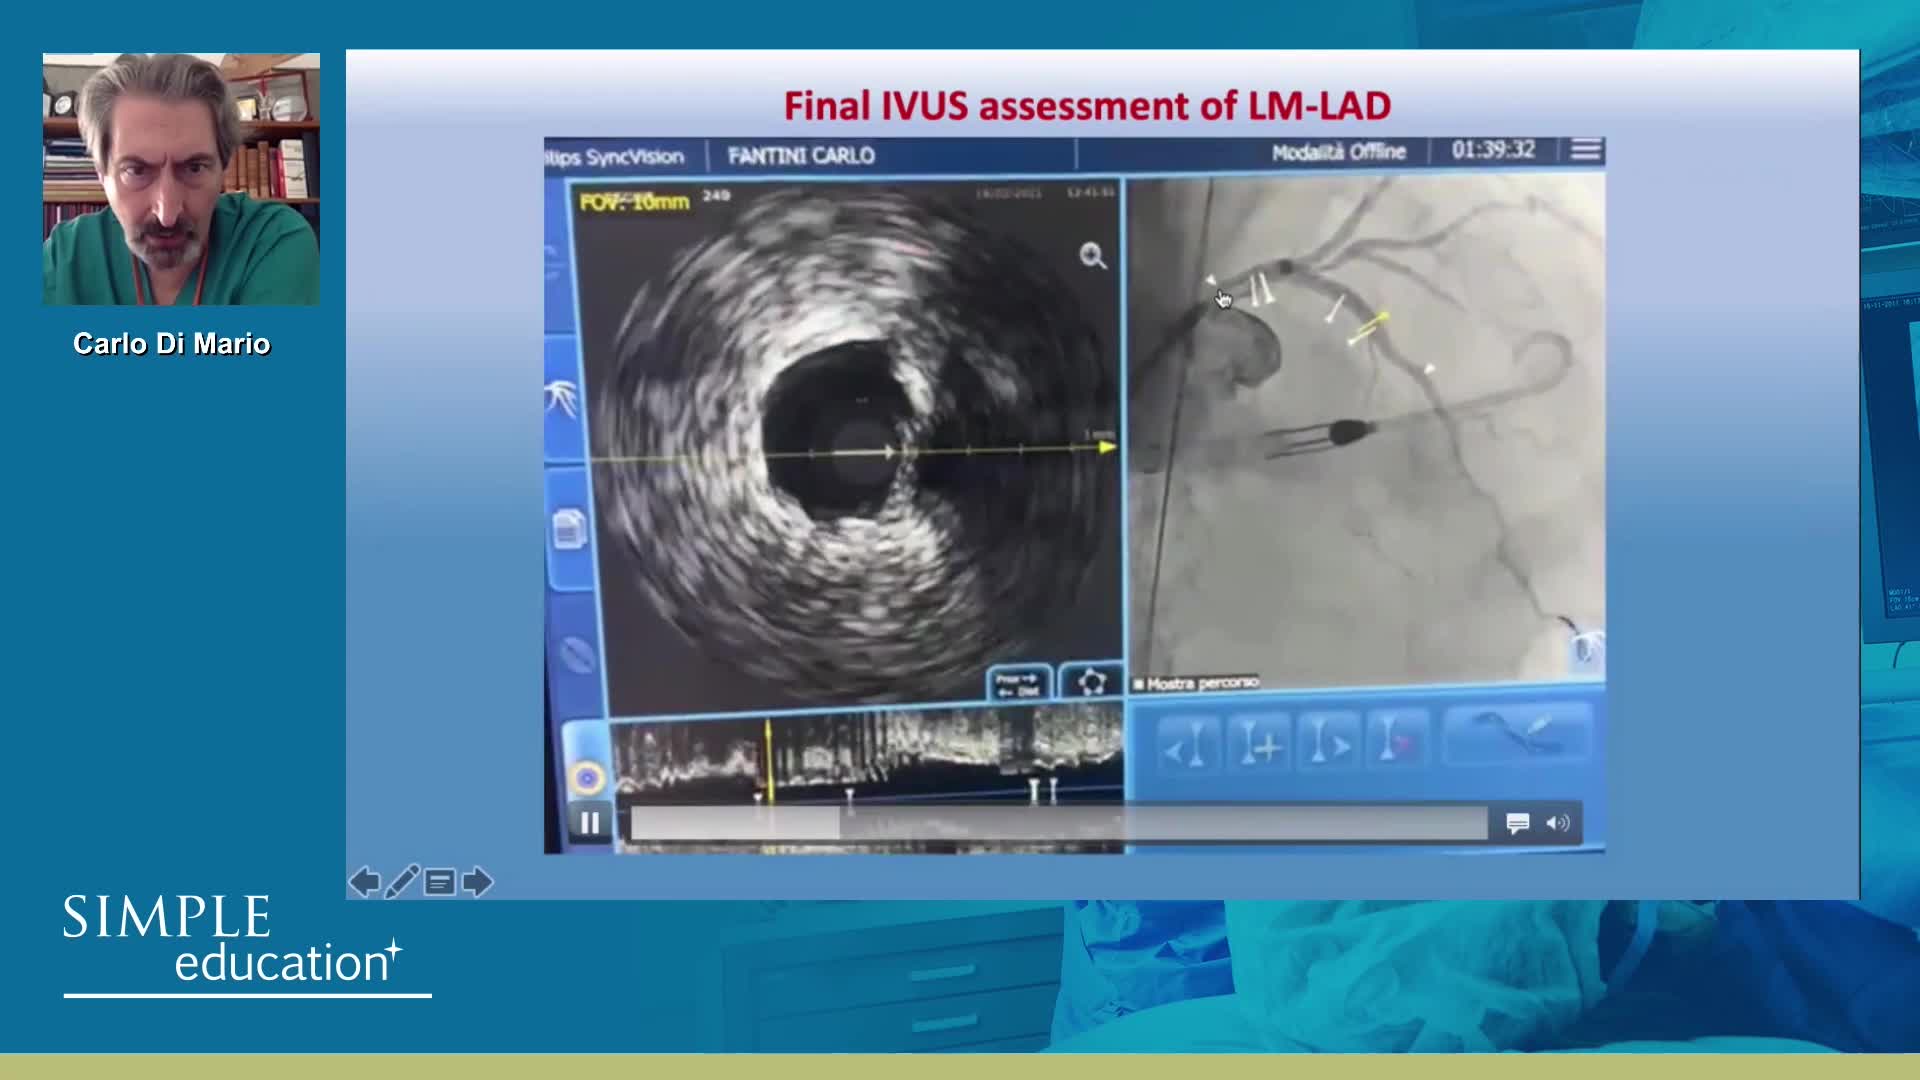

How to perform good co-registration measurements using iFR and IVUS - Prof Carlo Di Mario